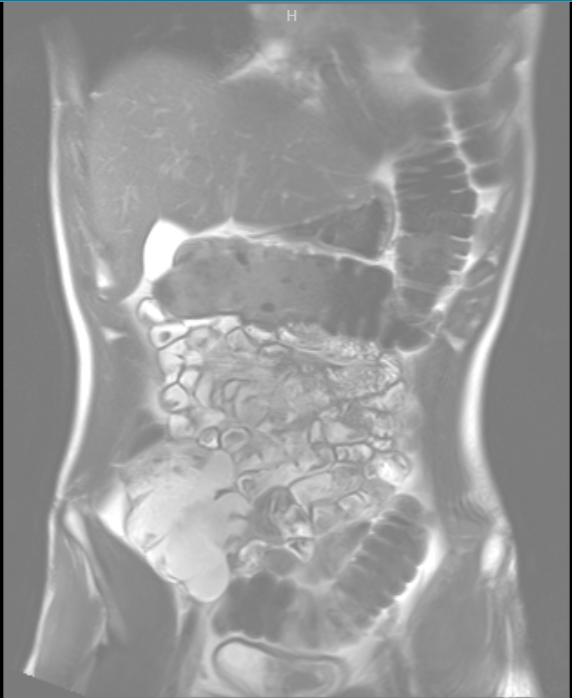

ЗАПОР 3 ГОДА Аноним 28/10/25 Втр 17:42:54 1646669 Ответ

image.png 303Кб, 556x687

image.png 250Кб, 572x698

Сап всем, у меня проблема с запорами не проходят 3 года. Мне 22 года, я обходил многих врачей. Сделал гастро и эндоскопию и ничего не выявили. Сделал мрт живота(прикрыл), и единственное что у меня выявили это "Удлинённая сигмовидная кишка(sigma elongatum)". Это возможно и причина проблемы. Проблем кроме запоров нет, я регулярно занимаюсь физическими активностями, нормальная диета и выпиваю по 2 литра воды в день.

Можете мне помочь с этой проблемой, мнение по этому вопросу от тех кто сталкивался с таким же или специалистов. Буду благодарен.